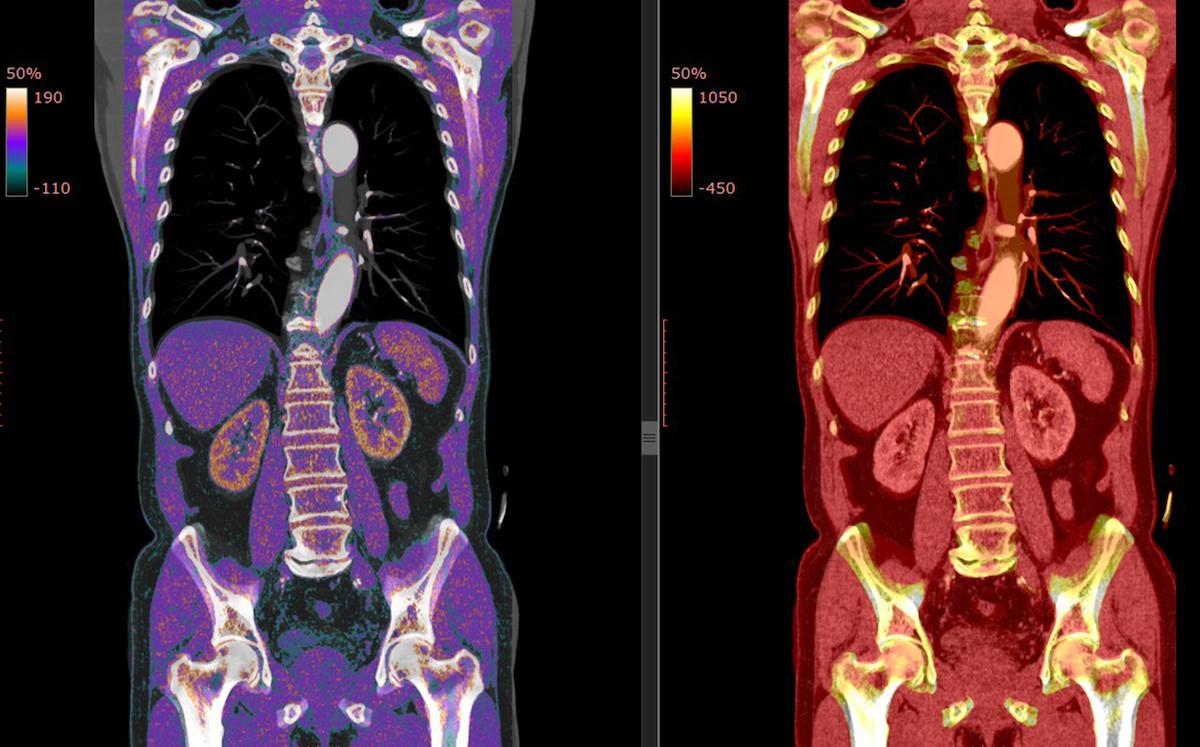

L’ostéomalacie induite par des tumeurs, dite « tumor-induced osteomalacia », est historiquement la forme acquise la plus fréquente d’hypophosphatémie liée au facteur de croissance fibroblastique 23 (FGF23). L’excès de FGF23 sécrété par la tumeur provoque une fuite rénale de phosphate, menant à des fragilités osseuses et à des douleurs osseuses diffuses. Le traitement de première intention consiste en l’ablation chirurgicale de la tumeur en cause. Toutefois, chez 27 à 45 % des patients suspects de cette pathologie, aucun foyer tumoral n’est décelable malgré des investigations exhaustives.

Dans une étude japonaise, des échantillons de sérum prélevés sur des patients et des témoins ont été soumis à une recherche d'auto-anticorps dirigés contre les protéines responsables de la FGF23rHR congénitale, notamment DMP1, ENPP1, FGFR1 et PHEX (phosphate-regulating endopeptidase X-linked). Ils ont tidentifié 13 patients avec des caractéristiques d’ostéomalacie liée à un excès de FGF23, mais sans tumeur détectable, après un criblage génétique et tumoral approfondi.

Les données présentées proviennent d’un processus de sélection rigoureux : tous les patients avaient un tableau clinique d’hypophosphatémie persistante et de fractures ou douleurs osseuses compatibles avec un excès de FGF23. Après exclusion des causes génétiques et tumorales (imagerie, examens biologiques, analyses génétiques ciblées), une analyse sérologique par immunoessai (LIPS) a été conduite pour rechercher la présence d’autoanticorps dirigés contre des protéines déjà incriminées dans les formes congénitales d’hypophosphatémie (DMP1, ENPP1, FGFR1 et PHEX). L’approche a été renforcée par cytométrie en flux, permettant de détecter d’éventuelles conformations antigéniques non décelées par la technique initiale.